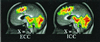

Medial prefrontal cortex (MPFC) is among those brain regions having the highest baseline metabolic activity at rest and one that exhibits decreases from this baseline across a wide variety of goal-directed behaviors in functional imaging studies. This high metabolic rate and this behavior suggest the existence of an organized mode of default brain function, elements of which may be either attenuated or enhanced. Extant data suggest that these MPFC regions may contribute to the neural instantiation of aspects of the multifaceted "self." We explore this important concept by targeting and manipulating elements of MPFC default state activity. In this functional magnetic resonance imaging (fMRI) study, subjects made two judgments, one self-referential, the other not, in response to affectively normed pictures: pleasant vs. unpleasant (an internally cued condition, ICC) and indoors vs. outdoors (an externally cued condition, ECC). The ICC was preferentially associated with activity increases along the dorsal MPFC. These increases were accompanied by decreases in both active task conditions in ventral MPFC. These results support the view that dorsal and ventral MPFC are differentially influenced by attentiondemanding tasks and explicitly self-referential tasks. The presence of self-referential mental activity appears to be associated with increases from the baseline in dorsal MPFC. Reductions in ventral MPFC occurred consistent with the fact that attention-demanding tasks attenuate emotional processing. We posit that both self-referential mental activity and emotional processing represent elements of the default state as represented by activity in MPFC. We suggest that a useful way to explore the neurobiology of the self is to explore the nature of default state activity.